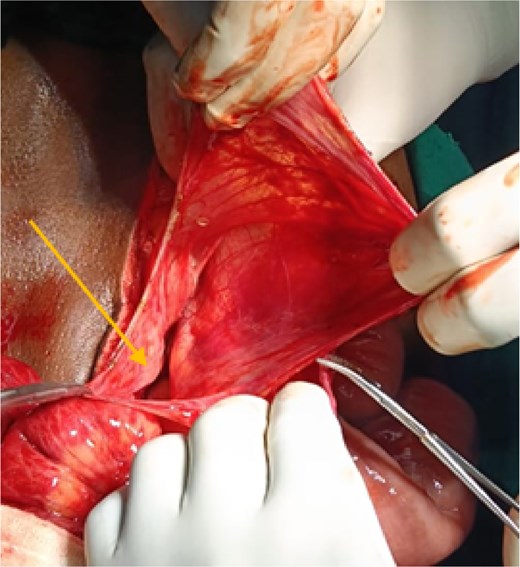

After initial resuscitation, the patient underwent emergency exploratory laparotomy. Intra-operatively, a large hernial sac was found near the third part of the duodenum behind ascending colon and right side of transverse colon containing gangrenous small bowel loops (Fig. 2). Lateral peritoneal attachments were divided and the caecum, ascending colon were mobilized medially representing the nonrotated gut. This manoeuvre exposed the underlying mesenteric defect. The hernial sac was opened widely which contained ileum and jejunum. After gentle reduction of the contents, the hernial opening was identified as a congenital defect adjacent to the third part of the duodenum, with the superior mesenteric vessels forming its medial boundary (Fig. 3). The margins of the defect within the mesocolon were carefully delineated and closed using absorbable 3-0 Vicryl in a continuous fashion (Fig. 4). Approximately 1 metre of gangrenous ileum, located 30 cm proximal to the ileocaecal junction, was resected. Given the patient’s hemodynamic instability and bowel condition, the proximal ileum was exteriorized as an end ileostomy in the left iliac fossa, and a distal mucus fistula was created in the right iliac fossa. The patient recovered well and was discharged on postoperative day 10.

Intraoperative picture showing hernial sac with bowel loops after reflecting ascending colon.